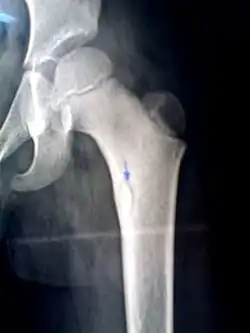

Sequestrum

A sequestrum (plural: sequestra) is a piece of dead bone[1] that has become separated during the process of necrosis from normal or sound bone.

It is a complication (sequela) of osteomyelitis. The pathological process is as follows:

- infection in the bone leads to an increase in intramedullary pressure due to inflammatory exudates

- the periosteum becomes stripped from the ostium, leading to vascular thrombosis

- bone necrosis follows due to lack of blood supply

- sequestra are formed

The sequestra are surrounded by sclerotic bone which is relatively avascular (without a blood supply). Within the bone itself, the haversian canals become blocked with scar tissue, and the bone becomes surrounded by thickened periosteum.